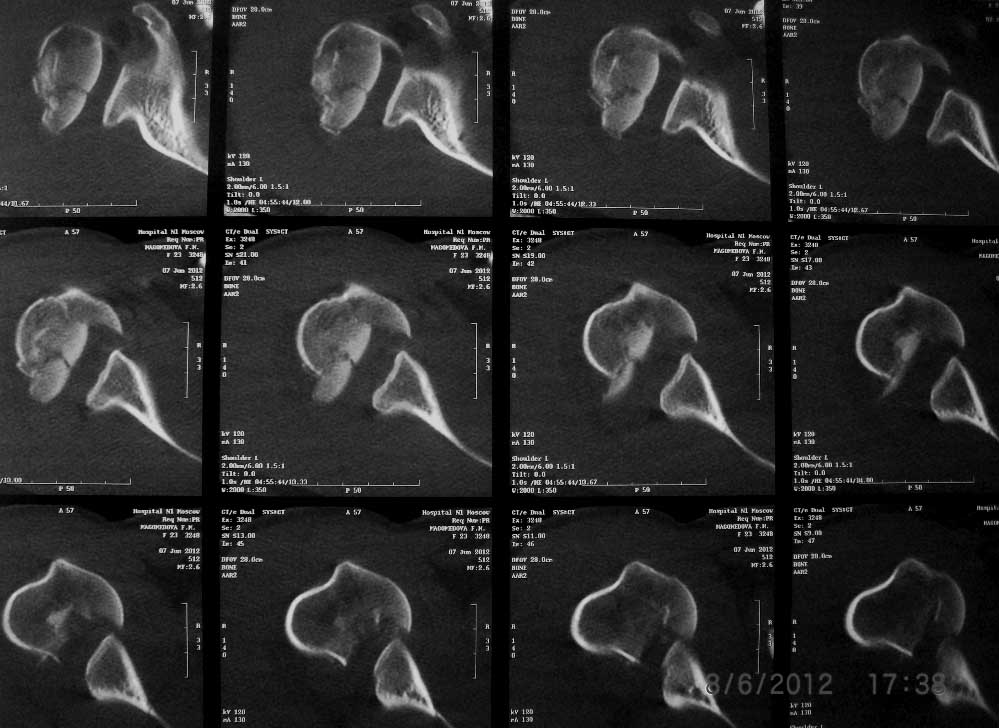

эндопротез и пластина. на томограмме - перелом головки плеча, синтезировать такое не получится

Такое впечатление, что у больной вывих плеча, с перелом большого бугра и переломом Хилл- Сакса. Вправить бы.. под наркозом, а потом решать (может мне показалось?)

мне тоже так показалось, надо бы КТ человеческое и аксиальный рентген

вывих похоже зажний с реверсивным х-с

В любом случае 23-летней пациентке надо сохранять свой плечевой сустав. То есть планировать открытую репозицию. Похоже, сломана только часть головки, так что повреждение не самое худшее. Бугорки на месте. Чем фиксировать - дело десятое. Хоть спицами. Можно и гвоздем из-за дистального перелома. Пластиной - не уверен, что есть смысл, перелома шейки нету здесь.

Какие-то снимки и срезы не самые информативные. 3D вообще черт-те что.